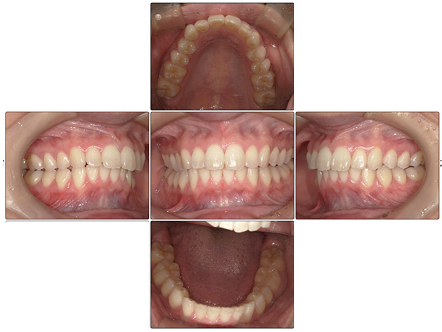

お口の中全体の写真

After

- 上の出っ歯は矯正治療前よりもひっこみ、前歯が全体的に整って綺麗な歯並びとなりました。